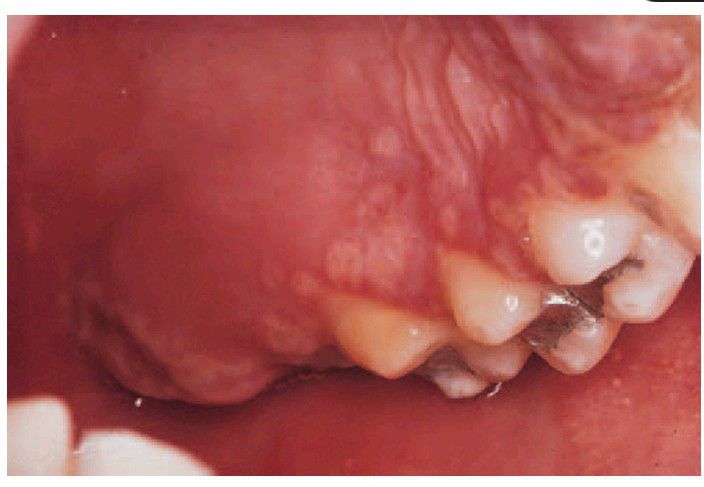

Herpetic stomatitis.

A group of recently ruptured vesicles on the hard palate, a characteristic site. The individual lesions are of remarkably uniform size but several have coalesced to form larger irregular ulcers.